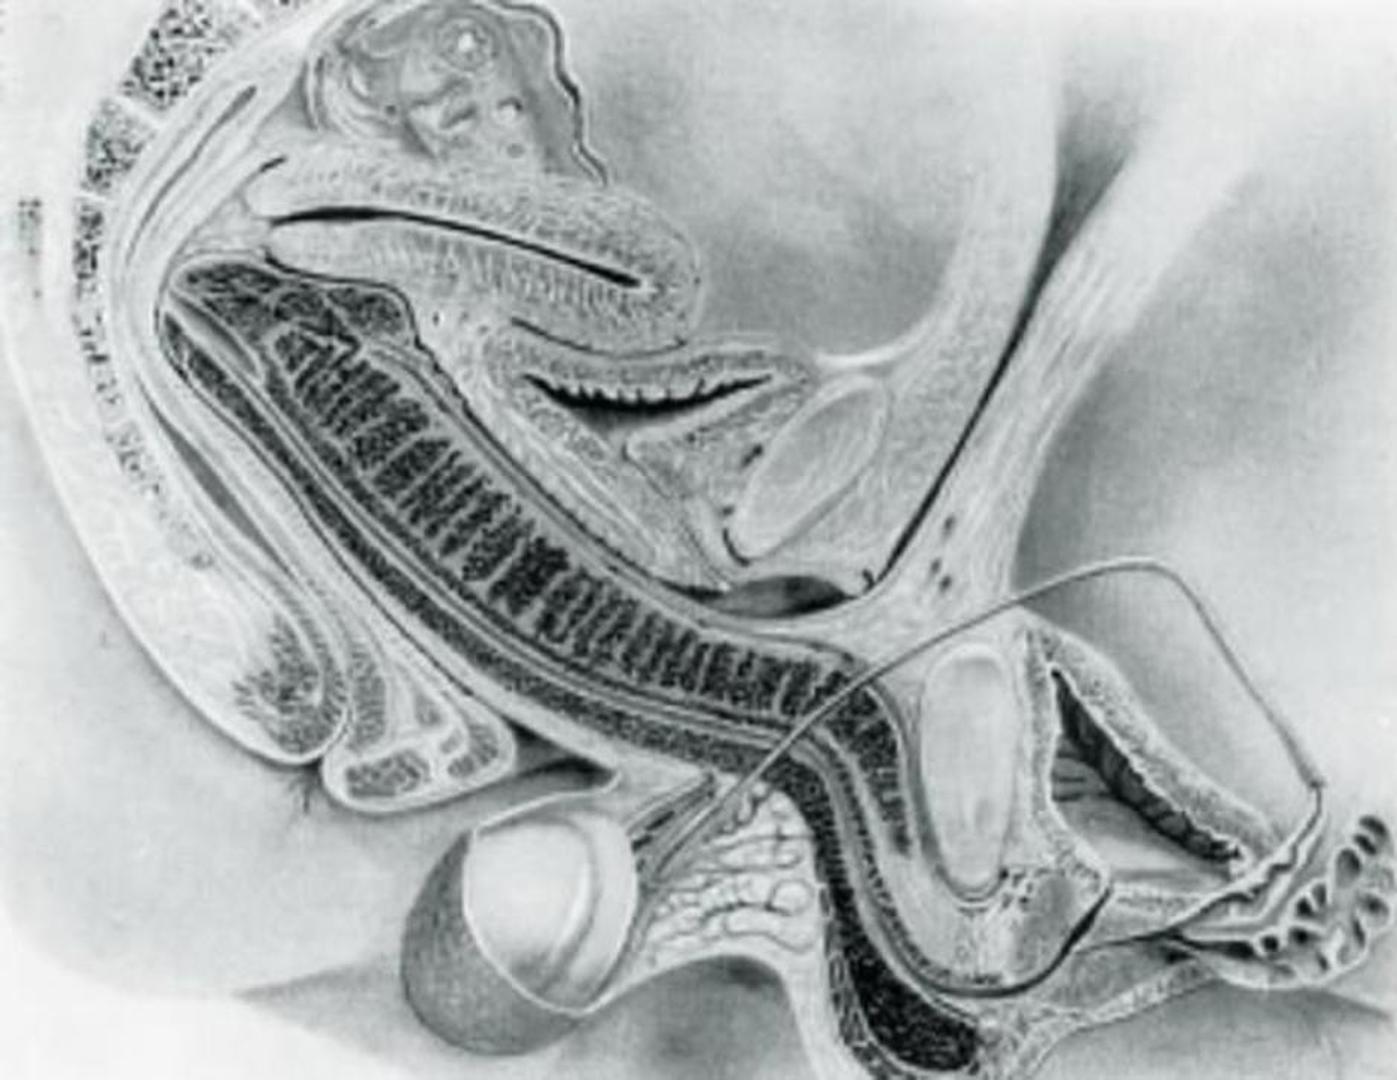

Britanski časopis British Medical Journal, to jest BMJ, objavio je prve MRI fotografije ljudi koji se seksaju, a i kažu kako su te fotografije popularne i 20 godina nakon objavljivanja. Fotografije su bile dio istraživanja, koje je promatralo parove kako se seksaju u raznim pozama, koje je objavljeno 1999. godine.

Glavno otkriće tog istraživanja je da penis poprima oblik bumeranga kada je u vagini, a do tada se mislilo da je ravan ili u obliku slova S.

Također je pokazalo kako se maternica ne povećava tijekom seksa, što se protivilo tadašnjem mišljenju.